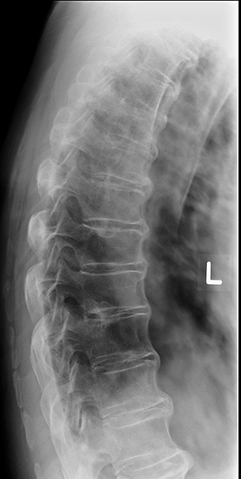

This is also known as "bamboo spine"

What is ankylosing spondylitis?